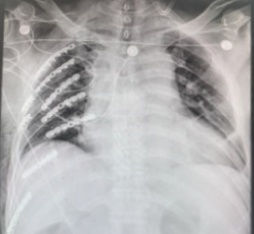

61岁的王先生和72岁的顾先生都是滑雪发烧友,在今年的雪季又驰骋在了雪白的世界。但极限运动总有风险发生,两位年过半百的运动健将不慎摔伤,造成了肋骨多根多段的骨折,且大多数骨折都位于肩胛骨后方。

通过MIPO微创钢板肋骨骨折固定,两位伤者在术后4天顺利出院,胸部疼痛基本消失,恢复上肢抬举功能。在完全康复后,相信明年又可以站上自己最爱的雪场。